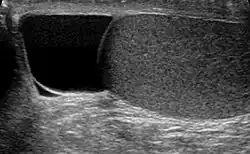

Ultrasound of a testicle (grey) and a spermatocele (black). | |

The primary care physician may diagnose and manage benign causes of scrotal masses such as hydrocele, varicocele and spermatocele. However, if a "must not miss" diagnosis related to testicular masses such as testicular torsion, epididymitis, acute orchitis, strangulated hernia and testicular cancer is suspected, the family physician must refer to a urologist.[19] Finding a painless, cystic mass at the head of the epididymis that is clearly separate from the testicle can indicate a spermatocele. Shining a light through the mass, a process known as transillumination, can also help differentiate between a fluid-filled cyst and a tumor, which would not allow as much light to pass.[20] If uncertainty exists, ultrasonography of the scrotum can confirm the presence of a spermatocele.[7] The location and history of any scrotal masses are crucial in determining whether or not the mass is benign or malignant.[21] Lab tests such as a complete blood count (CBC test) or urine test can also be conducted to check for any possible infection or signs of inflammation.[22]